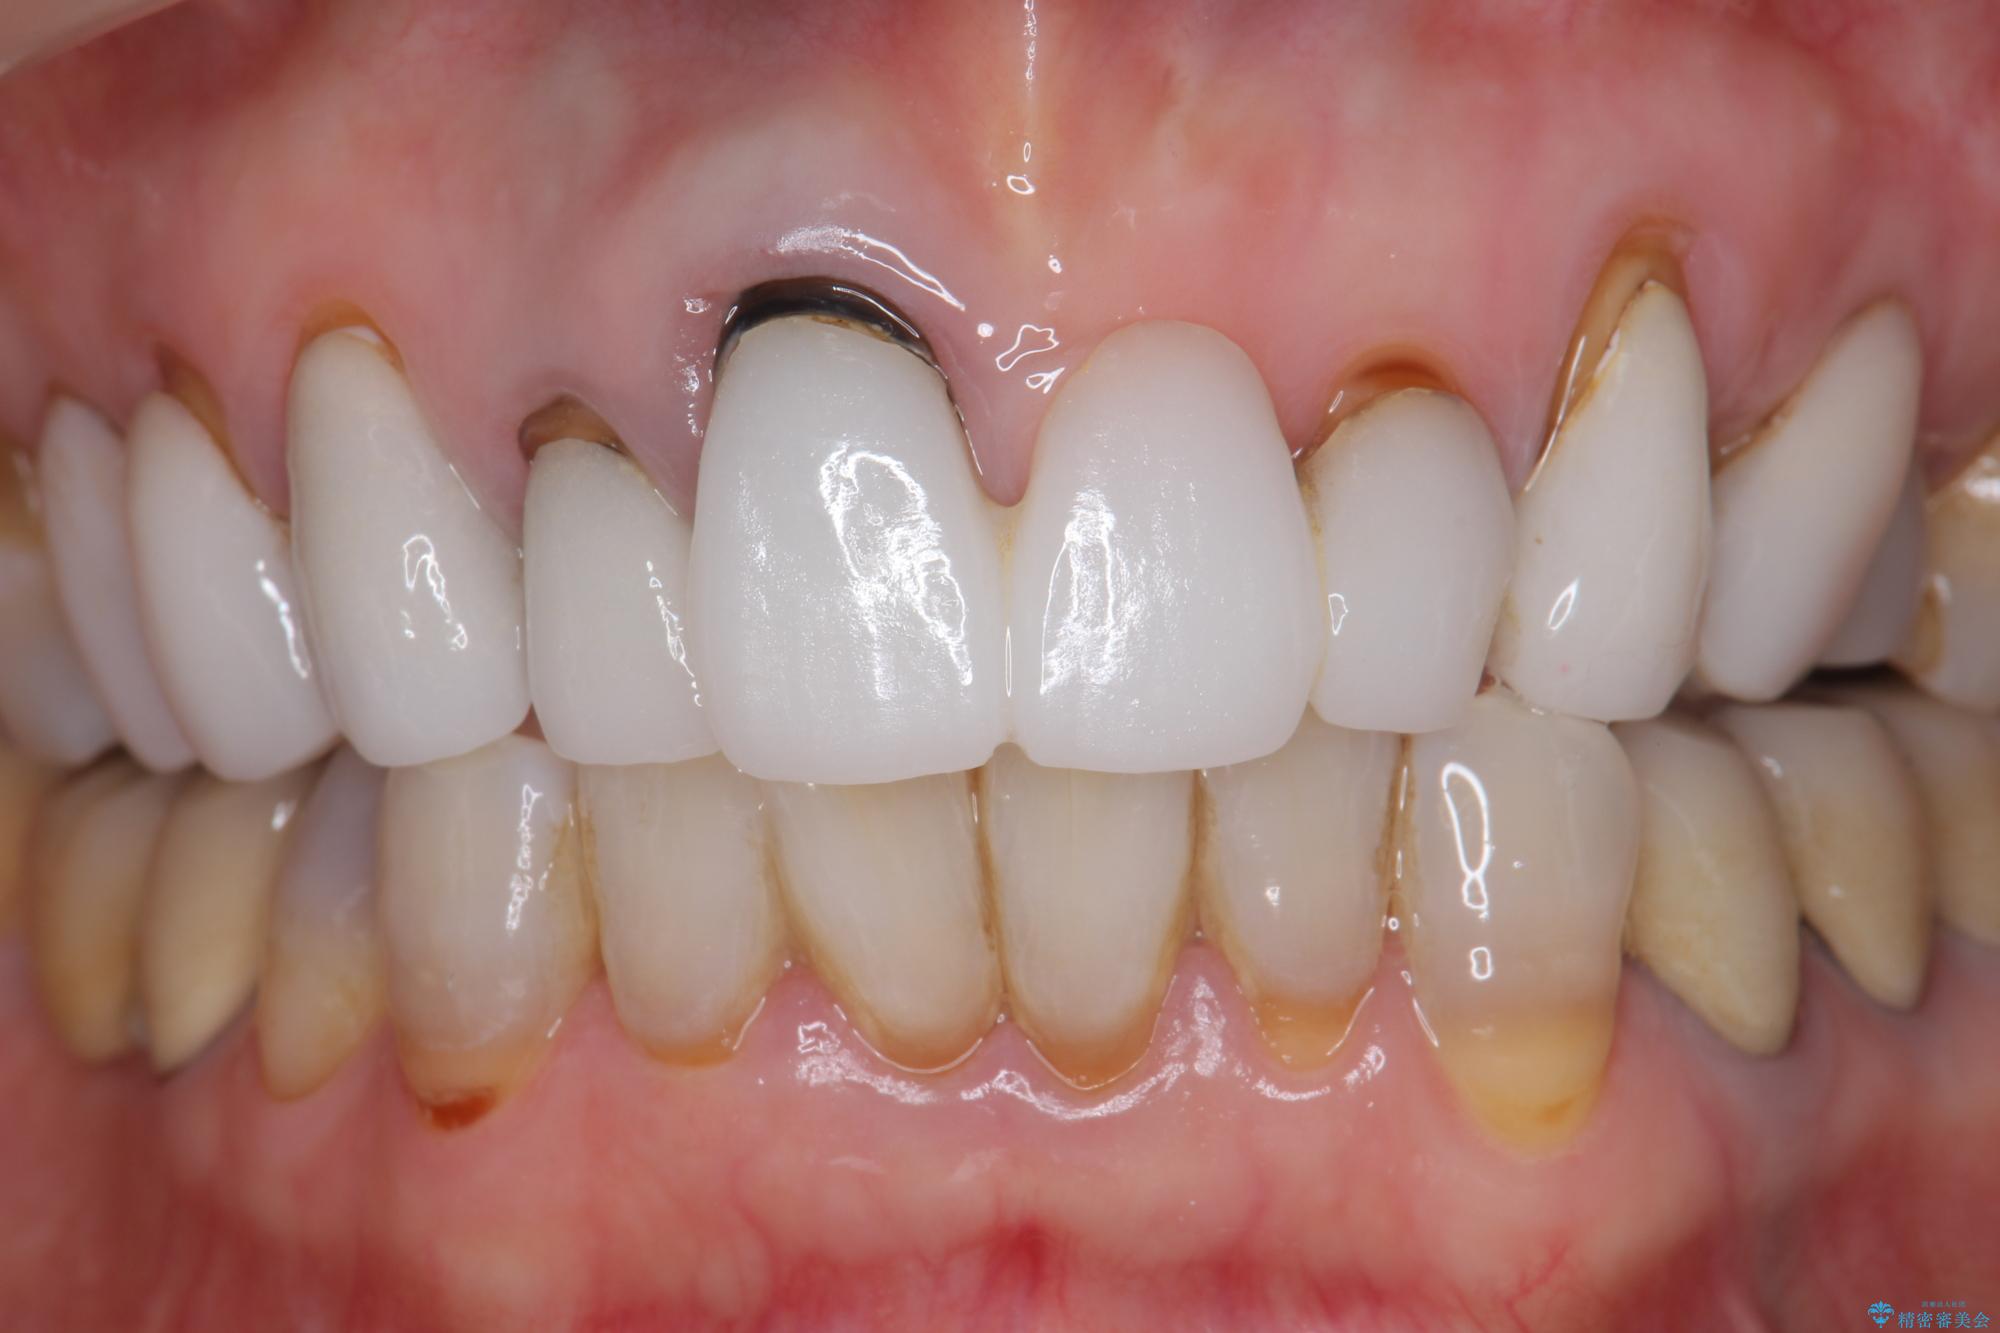

[ セラミック治療 ] 歯ぐきの際の黒ずみを改善したい

- 歯ぐきとセラミックの間の黒ずみが目立つので、きれいに治してほしい。と希望され来院されました。

歯ぐきの位置が変化しクラウン下の歯が見えるようになってしまったことで、審美障害が生じている状態です。

クラウンマージンの再設定を行うことで、黒ずんだ部分を再度覆い、審美障害を改善します。

- 52.8万円(ジルコニアクラウン×4・仮歯×4)費用は治療当時の料金となります